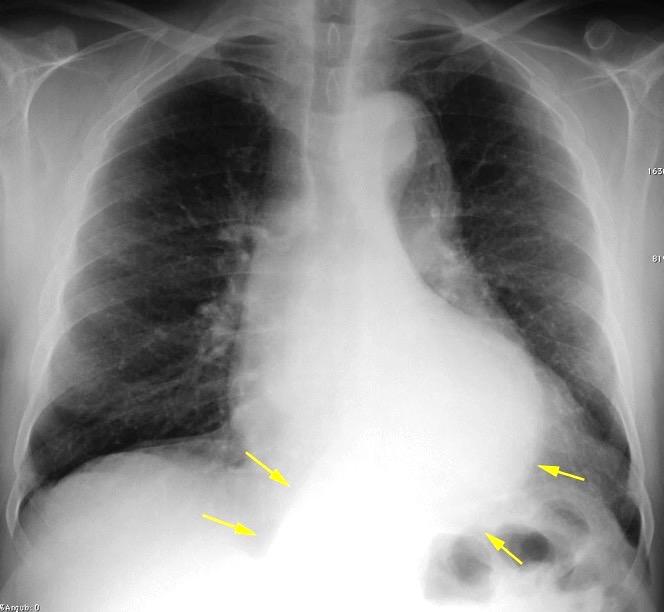

Líneas paraespinales formando un “paréntesis” por encima del diafragma. El signo señala el origen “intratorácico” de la lesión.

Conrad A et al. Pott’s disease associated with large and multiple abscesses in a 30-year-old migrant from Chad. BMJ Case Rep 2018

(lesiones toracoabdominales) La divergencia de las líneas paraespinales apunta a lesión toracoabdominal, que desde el tórax desciende y penetra en el abdomen.

Signo del “iceberg” positivo en Tb vertebral

Afectación por vía hematógena. Región dorsolumbar más frecuente. Afectación inicial: irregularidad de los platillos vertebrales, disminución del disco intervertebral con esclerosis ósea adyacente. Kim. Radiographics.2001